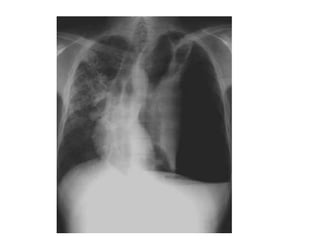

• #51 Paciente masculino de 63 años que refiere tos, disnea y dolor torácico derecho de aproximadamente siete días de evolución. El examen físico revela hipo ventilación en hemitorax derecho. Como dato positivo de laboratorio presenta VSG aumentada. Se solicita inicialmente una radiografía de tórax frente en la cual se observa, radioopacidad basal derecha con broncograma aéreo que borra el seno costofrénico homolateral. Engrosamiento pleural difuso que impresiona comprometer pleura mediastínica. Dados los hallazgos en la radiografía se decide ampliar el diagnostico solicitándole una TAC de tórax con contraste endovenoso en la cual se observa engrosamiento circunferencial pleural de hemitorax derecho. Atelectasia de segmentos inferiores con broncograma aéreo. Pequeña área líquida tabicada. Adenomegalias mediastinales en región prevascular, pretraqueal retrocavo y ventana aortopulmonar. Caja torácica sin alteraciones tomográficamente demostrables. Estructura y densitometría osteoarticular de l raquis dorsal normal. DIAGNOSTICOS DIFERENCIALES: • Engrosamiento pleural: Derrame organizado, hemotórax, piotorax, cirugía previa, radioterapia, exposición al Asbesto. • Tumores Benignos: lipomas, tumores fibrosos, esplenosis torácica. • Tumores malignos: MTTS de pulmón, mama, linfoma. • Mesotelioma maligno. DIAGNOSTICO DEFINITIVO: • MESOTELIOMA MALIGO